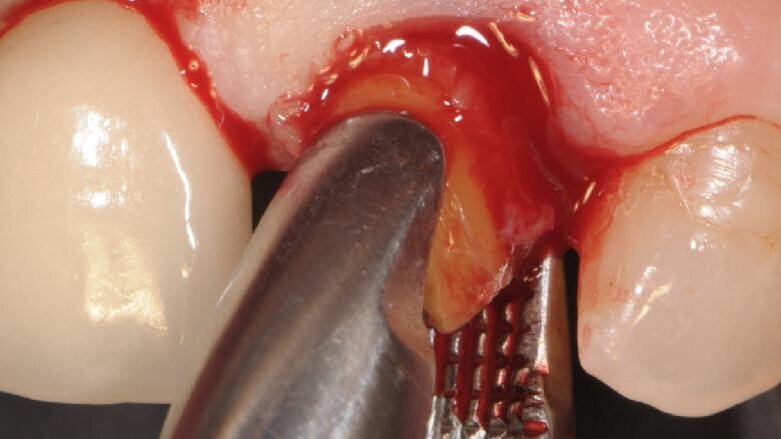

In paziente di sesso femminile ASA1, non fumatrice con ricostruzione endo-protesica su 1.1 e 2.1 si evidenzia un’irrimediabile frattura verticale di 2.1 con perdita di una estesa porzione coronale (Fig. 1), confermata dalla radiografia endorale eseguita con centratore (Fig. 2). Al sondaggio non si percepisce perdita ossea a livello circonferenziale. Nella stessa seduta si procede ad avulsione radicolare cercando di non lesionare la struttura ossea e conservando anche le limitrofe papille. Data la richiesta di estetica manifestata dalla paziente e il miglioramento di entrambe le corone cliniche si procede con l’inserimento di un’impianto endosseo secondo la tecnica postestrattiva immediata e contestuale posizionamento di provvisorio con l’unione di entrambe le corone protesiche.

Fig. 1 - Visione al momento della prima visita in cui la paziente aveva fratturato la radice in senso verticale smarrendo la corona.

Fig. 3 - Estrazione della radice eseguita con particolare attenzione al ridotto traumatismo del tessuto osseo e mucoso circostante.